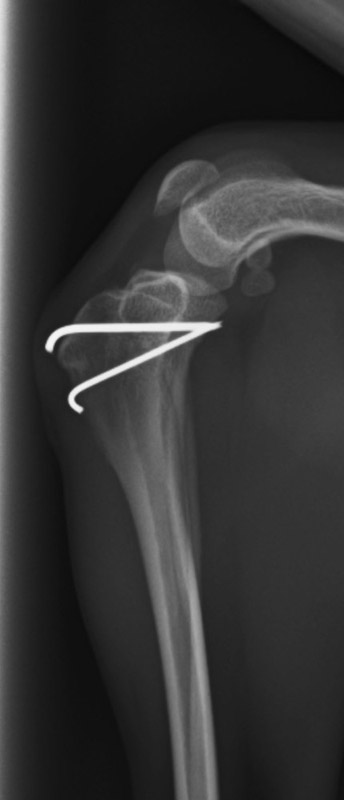

肘関節内骨折

アメリカン・コッカー・スパニエル(5歳)

車の窓から落下

手術前

手術後